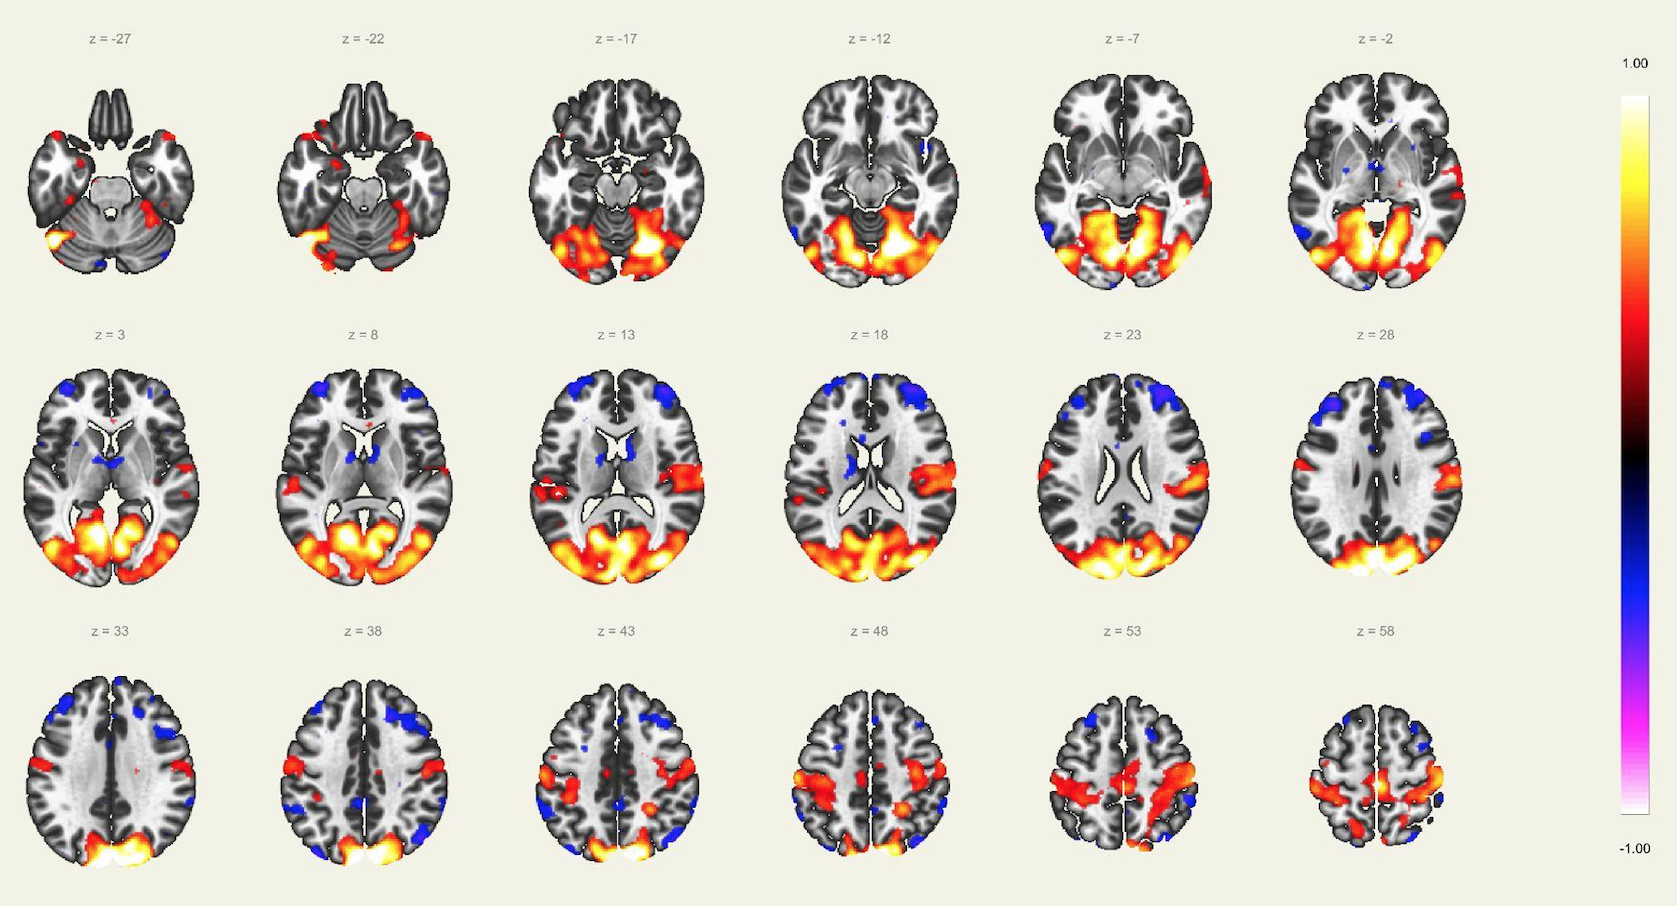

En este estudio, el escaneo se realizó con un resonador de 3 Tesla del servicio de diagnóstico por imágenes de la Clínica Internacional, a un paciente joven, sin comorbilidades ni antecedentes de importancia, el cual estuvo despierto en todo momento y con los ojos cerrados. Además, se le dio instrucciones de completar palabras mentalmente sin emitir sonido alguno o hacer gestos, llegando a identificarse las distintas redes cerebrales detalladas posteriormente.

El estudio fue realizado con secuencia BOLD, con los siguientes parámetros: cortes: 40, factor de distancia: 0%, Field of View: 240 mm, grosor de corte: 4 mm, tamaño de vóxel: 3.8 x 3.8 x 4 mm, TR: 3000 ms, TE: 30 ms, Umbral: 4 y tamaño del paradigma 20.

A pesar de la ausencia actividad física, resulta imposible indicar que no se esté realizando ningún tipo de actividad mental, como recuerdos o el uso de la imaginación. La consecuencia de esto se ve reflejada en los cambios de la actividad neuronal.16 A través de este método de vóxel semilla se ha logrado identificar distintas redes de conectividad funcional descritos a continuación:

Red Ejecutiva y Red del Control Ejecutivo

La red ejecutiva es la red que se activa al realizar exámenes como la resonancia magnética funcional basada en tareas, y se encuentra compuesta por la corteza prefrontal dorsolateral y corteza parietal posterior. Mientras que la red del control ejecutivo comprende el giro frontal medio, giro frontal superior, la corteza anterior del cíngulo, giro paracingular, corteza prefrontal ventrolateral y regiones subcorticales del tálamo. Esta red se activa durante las tareas que requieren el uso de la cognición y memoria procedimental. Principalmente suele verse en caso de actividades dirigidas y durante la realización de actividades intelectuales.

Red Sensorio-Motora:

Primera red en ser estudiada usando el método de vóxel semilla, la cual muestra la alta correlación entre las regiones motoras del hemisferio izquierdo y derecho. En esta corteza sensorio-motora, las áreas de Broddman, localizadas en la región posterior al surco central, el giro precentral y la corteza auditiva primaria, forman parte de esta red, en asociación con los núcleos ventral laterales y ventral posterior del tálamo. La activación de esta red interviene directamente en la percepción de estímulos sensorio-motores, auditivos y en el planeamiento y ejecución para el movimiento de los músculos.

Red Auditiva:

Red asociada a la red sensorio motora, comprendido por la corteza auditiva primaria bilateral, giro temporal transverso, planum polare y temporale, giro temporal supero-lateral y corteza insular posterior. Las cortezas auditivas se encuentran bien definidas para como confiables para el giro temporal transverso de cada lado respectivamente.